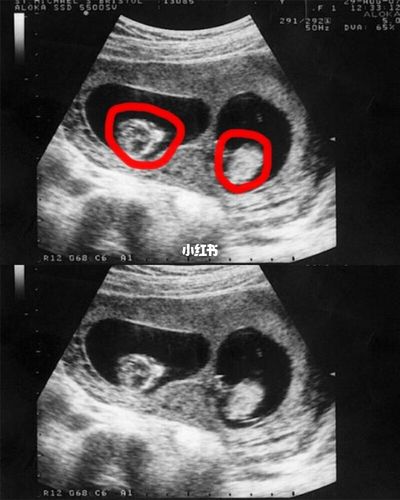

怀双胞胎第一个月症状,很多人都特别好奇,是不是和单胎的生长一样,从一怀孕开始单胎的症状就已经提前出现了。那么,怀双胞胎第一个月症状有哪些?下面,我们就来了解一下这个话题。

首先,其实怀双胞胎的孕妈妈可能会比单胎的孕妈妈更容易感觉到不舒服。怀双胞胎的妈妈相比单胎的孕妈妈更容易感觉到不舒服,特别是怀双胞胎的妈妈在怀孕的头两个月,随着子宫的增大,宝宝与妈妈之间的接触增加,肚子越来越大,耻骨痛、腰背痛等症状可能会更加明显。

其次,怀双胞胎的妈妈和单胎的妈妈存在一个差异,可能会更容易感觉到不舒服。由于两个宝宝在子宫里生长发育不一样,所以宝宝体位也会存在着不同。怀双胞胎的妈妈比单胎的妈妈更容易感觉到不舒服。

最后,妈网百科也说了,怀双胞胎第一个月的症状主要是感受到了宝宝在子宫里的活动,尤其是怀孕的前几个月,孕妈妈会感觉到明显的胎动。另外,怀双胞胎第一个月的症状明显起来了。